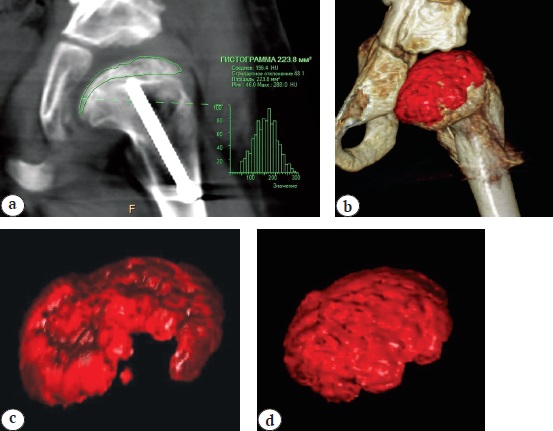

The results of MSCT of the hip joints showed that in all patients, during the initial studies, there was a total lesion of the femoral head with partial preservation of the marginal surfaces of the epiphysis. The subchondral necrosis zone was measured when assessing the height of the lateral, central and medial parts of the head. A total decrease in the height of the central part was observed in 30% of patients, subtotal — in 70%. Densitometric characteristics of the density of the fragmented femoral head according to the histogram showed increased mineralization by an average of 81.8 ±15.9 units. Houndsfield (HU) compared with a healthy femoral head (Fig. 2).

Fig. 2. Computed tomography of the hip in a patient with Perthes disease (Catterall IV) and hip subluxation: a — method of measuring the zone of subchondral necrosis; b — assessment of femoral head density using the histogram technique of the allocated volume of the studied zone

It can be seen from Table 4 that all patients had elimination of subluxation with restoration of hip joint stability, as evidenced by the changes in the Sharp, Wiberg, and DBC angles (p<0.05). The moderately pronounced excess of the lower limit of the normal values of the Sharp angle is explained by the need for a greater intraoperative lateral inclination of the acetabulum than in children with hip dysplasia due to the presence of a destroyed lateral column of the femoral head and coxa magna forming, as well as its initially smaller deformation. The results of the MSCT showed that the structure of the femoral head bone tissue in dynamics allowed differentiating the initial elements of the trabecular pattern in comparison with the homogeneous high-intensity structure of the head initially, and the densitometric characteristics of the femoral head density, according to the histogram, began to approach the values on the contralateral proximal epiphysis. In all patients, during the control study, the restoration of the shape of the head was noted in the form of both an increase in the size of the lateral parts (mainly lateral) and a decrease in the area of the head defect or lack of compression of the central part of the epiphysis — a significant improvement in the shape of the femoral head with the appearance of its single bone contour. With volumetry, the volume of the bone part of the head increased by 15-35% (2-3 cm3) from the initial values (Fig. 5).

Fig. 5. Computed tomography of the hip: volumetric and multiplanar reconstructions and tissue segmentation (color mapping of the affected head) with the measurement of its volume: a — assessment of the densitometric parameters of the femoral head density using the histogram technique of the selected volume of the area under study; b — measurement of the volume of the affected head by multiplanar reconstruction with color mapping; c — measurement of the bone mass volume of the affected head before surgery; d — 6 months after surgery